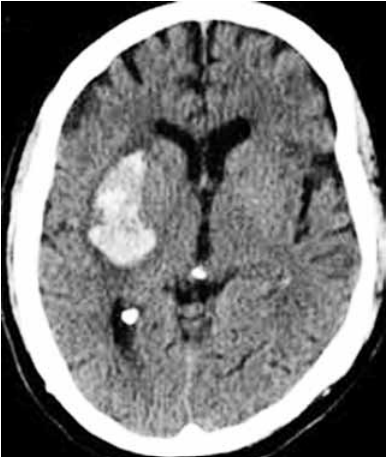

Paciente do sexo masculino, 58 anos, hipertenso prévio sem controle adequado e tabagista. Admitido com queixa de cefaleia e hemiplegia completa à esquerda de início súbito há 4 horas da admissão hospitalar. No momento apresenta pontuação na escala do NIH de 12, pressão arterial de 210/100 mmHg, FC: 87 bpm, ritmo sinusal no monitor cardíaco. Tomografia de crânio a seguir.

Assinale a alternativa correta referente ao tratamento na fase aguda desse paciente.